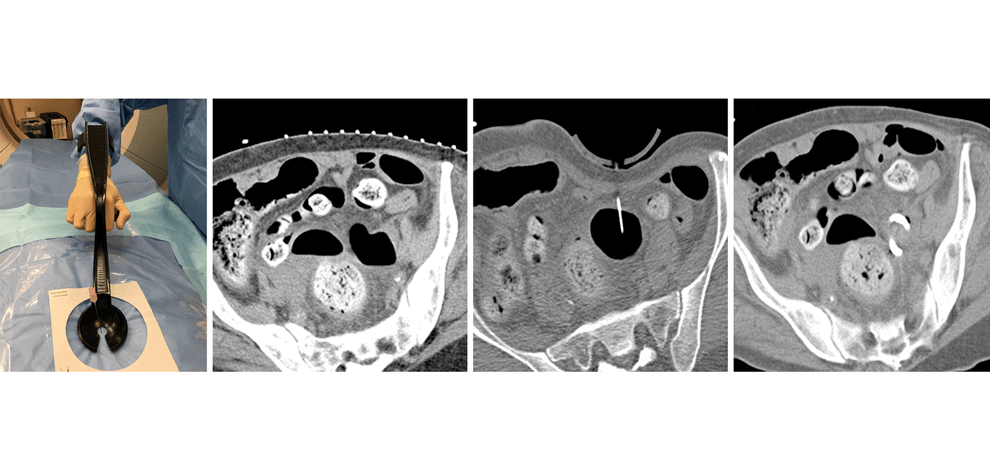

The device was used to perform

18 biopsies, two abscess drainages,

and one liver microwave ablation.

It was particularly useful when bowel loops were

found to preclude safe needle access to the

target, when mobility of the target made targeting

difficult, and when bowel was too

close to the planned ablation zone.